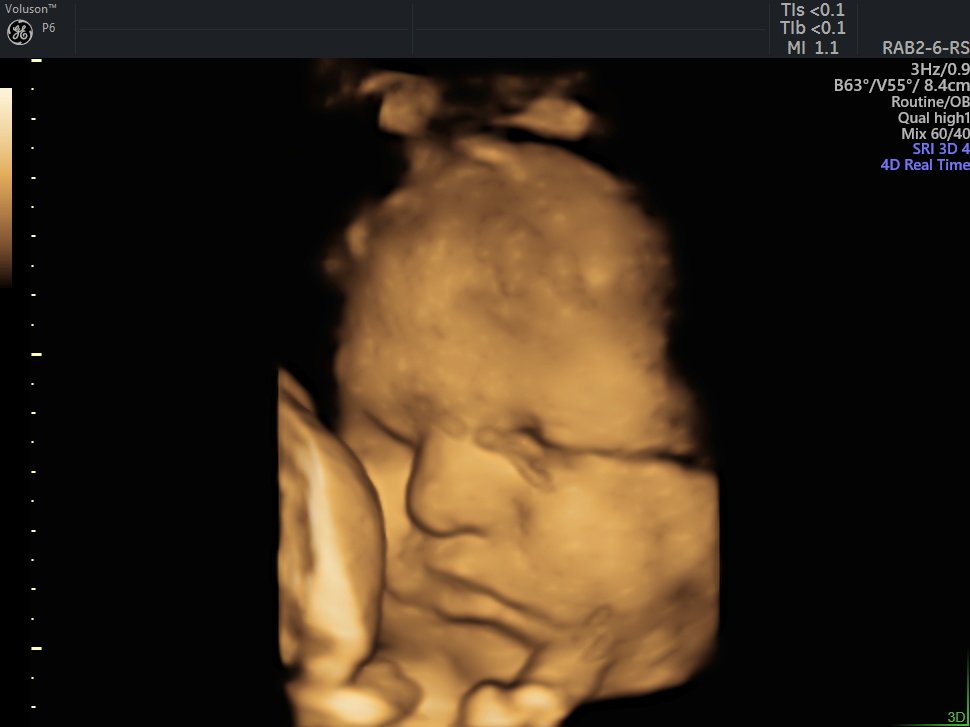

4 Boyutlu (Renkli) Ultrason ve Doppler Ultrasonografi

4 D Ultrasonografi